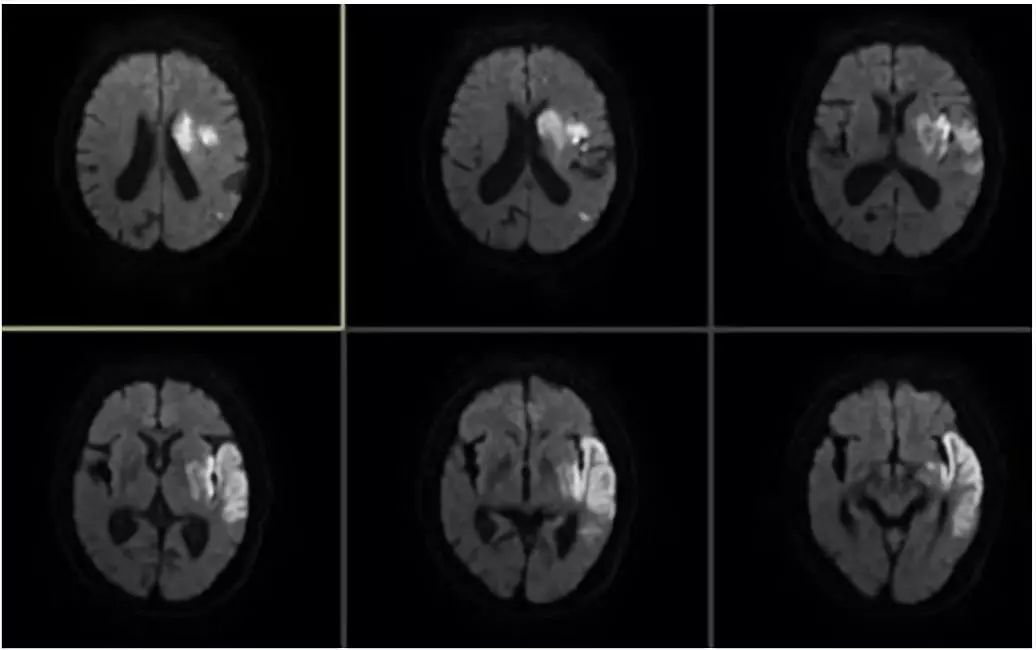

术后复查头MRI示(图9)

图9

患者术后替罗非班泵入24小时,再过度使用阿斯匹林100mg、氯吡格雷75mg抗栓及瑞舒伐他汀20mg口服强化降脂稳定斑块治疗。术后第3天,患者肢体无力症状恢复正常,混合性失语症状较前好转,NIHSS评分:2分。术后90天门诊随诊时,遗留轻度失语,mRS评分1分。